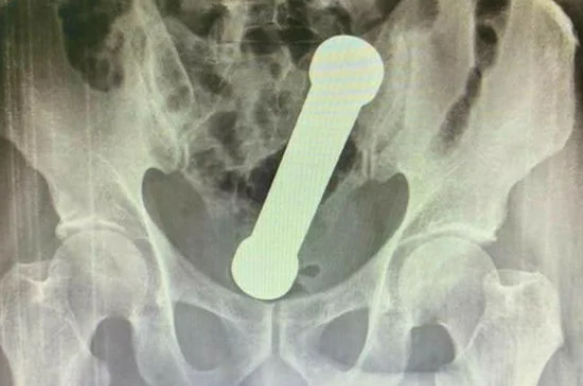

Peso foi visto dentro do homem durante um exame de raio-X – Foto: Reprodução/NDPeso foi visto dentro do homem durante um exame de raio-X – Foto: Reprodução/ND

Em um exame de raio-X, os médicos encontraram um peso de academia de dois quilos, de cerca de 20 centímetros de comprimento, dentro do homem. O haltere estava entre o reto e o intestino grosso do paciente. Depois do exame, ele admitiu ter introduzido o objeto no corpo para obter satisfação sexual.

Paciente precisou ser sedado para a retirada do objeto – Foto: Reprodução/NDPaciente precisou ser sedado para a retirada do objeto – Foto: Reprodução/ND